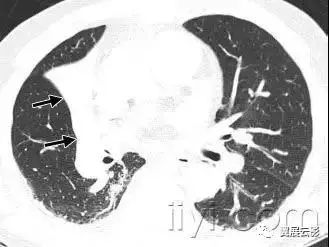

十八、小叶中心性:

解剖:小叶中心性用于描述次级肺小叶的支气管血管束中心区域。病理学上也用这一术语描述终末小支气管远端,位于呼吸性细支气管和肺泡管中心的病变。

CT:正常次级肺小叶中心的点状或者线状的密度增高影,胸膜下25px范围内最明显,代表小叶内的动脉,直径约1mm。

小叶中心性异常包括(1)结节(2)树芽征,提示小气道病变(3)由于临近间质的增厚或者浸润导致小叶中心结果更加清晰(4)小叶中心性肺气肿导致的异常低密度。

附图为小叶中心性肺气肿